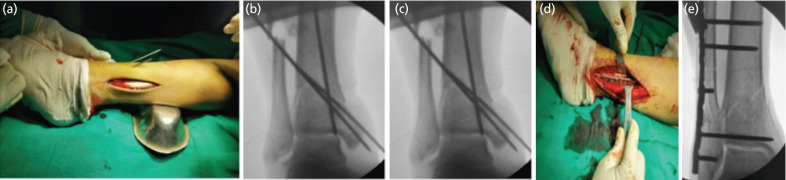

Introduction: Despite recent advances, management of distal tibial fractures is challenging, with high rate of complications. Fibula pro tibia plating technique fixes fibula and tibia together, via laterally placed fibular plate without disturbing the tibial soft tissue sleeve. We contemplated this pilot study to assess effectiveness of fibula pro tibia plating in management of distal tibia fibula fractures.

Materials and methods: A total of 30 patients with distal tibia fibula fractures with fracture line extending within 5cm from tibial plafond were managed with fibula pro tibia plating, with or without minimal articular fixation. Outcome evaluation was done by union, union time, alignment and functional outcome as assessed by AOFAS score.

Conclusion: Fibula pro tibia plating can be successfully used to manage complex distal tibia fractures which leaves the soft tissue and periosteal sleeve undisturbed, thus avoiding wound related problems and leading to early union.